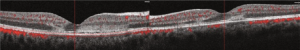

- Spectral domain optical coherence tomography (OCT): Hyperreflectivity from the outer plexiform layer to the RPE in acute lesions, with normal retinal thickness.[6] Absence of the ellipsoid zone (EZ) may also indicate foveal involvement and correlate with the loss of visual acuity.[19] Hyperreflectivity of outer layers disappears, the EZ re-emerges, and focal photoreceptor/RPE atrophy occurs during resolution of the placoid lesions.[6][19][20]